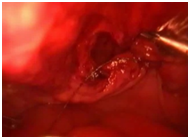

Diagnostic and treatment processes of patients was carried out according to the diagnostic algorithm developed in the Republican research center for emergency medicine at injury of a bladder taking into account the dominating pathology. On this diagnostic algorithm taken patent from Agency on intellectual property of the Republic of Uzbekistan. No. DGU 2010 0177. The valuable diagnostic method of bladder injury is retrograde cystography. At doubtful cases CT more precisely allows to determine the volume and nature of bladder injury and to estimate condition of other associated lesions. At 5 (4.2%) patients the isolated injury of a bladder managed by laparoscopic repair of a bladder rupture on an urethral catheter (Figures 1 & 2).

Figure 2 3cm defect visualized at the dome of the bladder during laparoscopic repair.